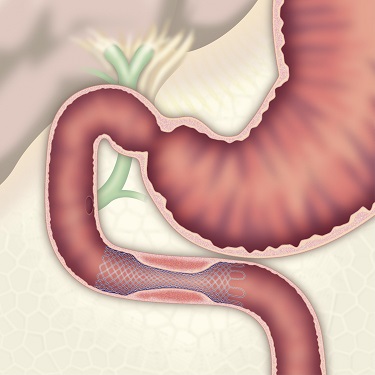

内視鏡的粘膜切除術(EMR)

外来にて切除することの出来ない、比較的大きめの大腸ポリープや平坦な病変などの切除の際に行います。

| 1:ポリープを見つけ、NBI併用拡大観察をした後、 | 2:ポリープ直下の粘膜下層に局注液を注入し盛り上げます。 | |

| 3:ポリープをスネアに通し、周囲の正常粘膜を入れて病変を絞扼 | 4:電気を流してして切除します。 | |